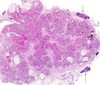

grade this disease

what is found in micro

high grade dysplasia or carcinoma in situ of esophagus

glandular architectural irregularity, nuclear atypia